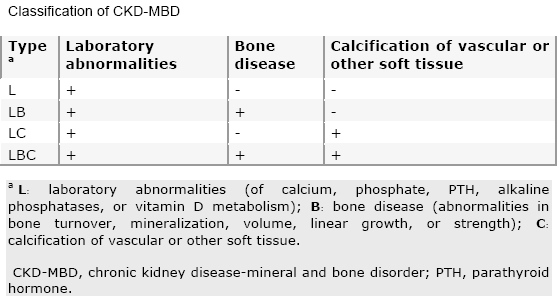

CKD-MBD נחשב כהפרעה סיסטמית (Systemic) המוגדרת על־ידי אחד מהשילובים הבאים:

לקוח מתוך: Kidney International 2006,69:1945-53, באישור של Nature Publishing Group בספטמבר 2009.